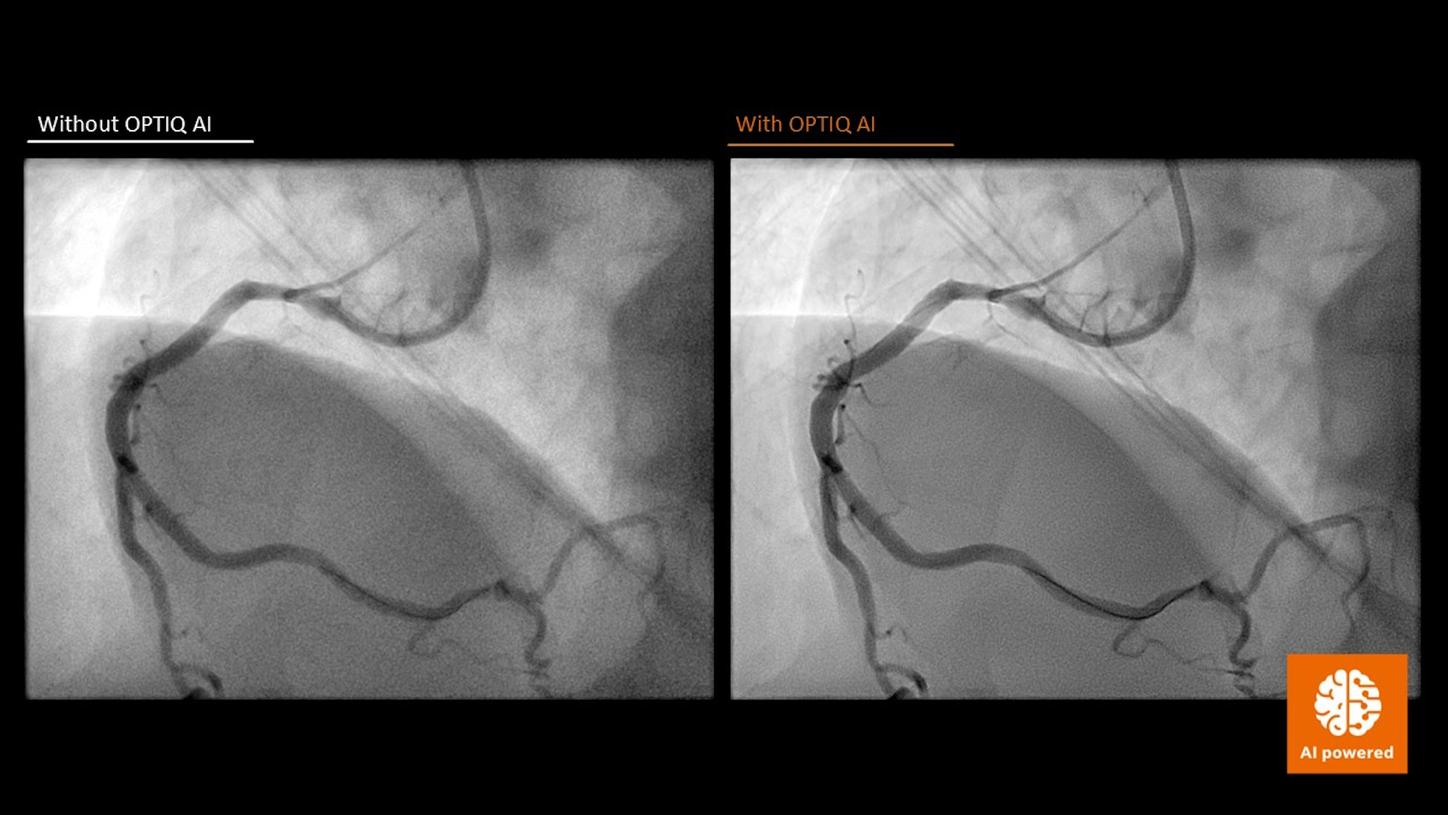

Courtesy Prof. Sossalla, MD, Kerckhoff-Klinik, Bad Nauheim, Germany

- OPTIQ AI consistently delivers images at the desired quality, defined by contrast-to-noise ratio, while minimizing radiation dose in accordance with the ALARA3 principle - throughout the procedure.

- Device visibility is automatically optimized based on the X-ray absorption characteristics of each material.

- An AI-powered algorithm reduces image noise in real time, preserving and visualizing the contained image structures more effectively4,5 across all 2D imaging modes6 and body regions.